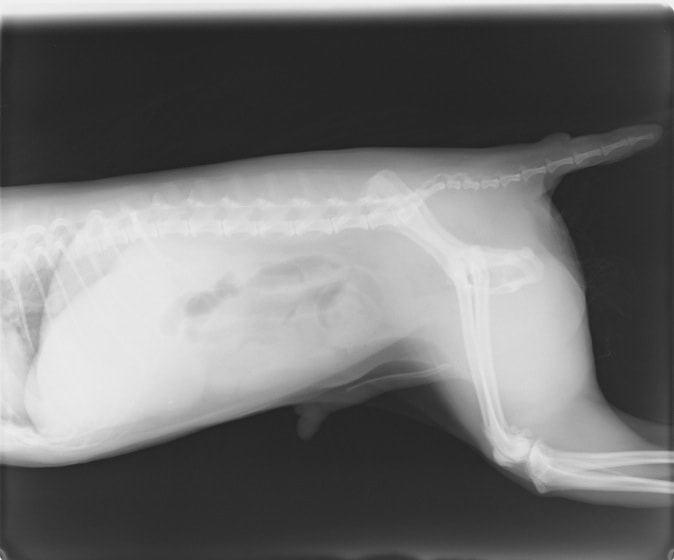

・ 胸部レントゲン検査:胸水貯留

レントゲン画像